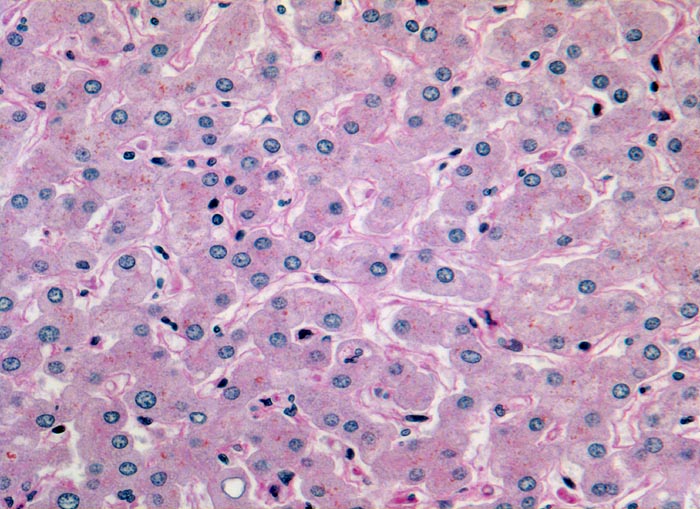

Leber HE

Leber bei Alpha-1-Antitrypsinmangel

Befund

Pathologischer Befund

Normalbefund